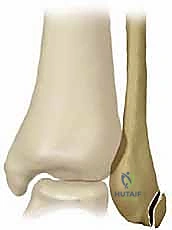

لفهم مشكلة انخلاع الأوتار الشظوية، يجب أولاً أن نفهم التشريح المعقد والدقيق للكاحل. توجد الأوتار الشظوية (Peroneal Tendons) في الجزء الخارجي (الجانبي) من الكاحل، خلف العظمة البارزة التي تُعرف باسم "الكعب الوحشي" (Lateral Malleolus). يتكون هذا النظام من وترين رئيسيين:

1. الوتر الشظوي الطويل (Peroneus Longus): يمتد أسفل القدم ليساعد في استقرار القوس الأخمصي.

2. الوتر الشظوي القصير (Peroneus Brevis): يلتصق بقاعدة العظمة المشطية الخامسة في القدم.

هذان الوتران يمران معاً داخل تجويف عظمي يُسمى "التلم الشظوي" (Fibular Groove). ولضمان بقاء هذه الأوتار في مكانها أثناء الحركة، يوجد شريط ليفي قوي يُسمى الرباط الشظوي العلوي (Superior Peroneal Retinaculum - SPR). وظيفة هذا الرباط هي تثبيت الأوتار ومنعها من الانزلاق أو الخروج من مسارها عند تحريك القدم للأسفل أو للأعلى.

يحدث انخلاع الأوتار الشظوية عندما يتمزق الرباط الشظوي العلوي (SPR) أو يرتخي بشدة، مما يسمح للأوتار بالانزلاق والخروج من التلم العظمي الخاص بها لتستقر فوق العظمة الجانبية للكاحل.